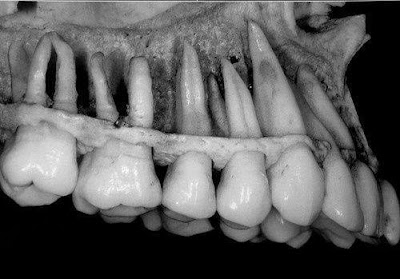

Nuestros especialistas en Monterrey utilizan tecnología de vanguardia como radiografía digital, escáneres intraorales 3D y blanqueamiento láser, garantizando diagnósticos precisos y tratamientos menos invasivos.